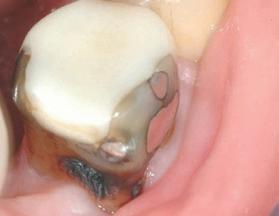

Estelite Asteria (Tokuyama)One of my favourite composite resin materials is Asteria which is a light-cured radiopaque composite for universal use. It considerably simplifies multilayer techniques yet delivers outstanding aesthetics with excellent polishability. Unlike mul tilayer techniques used with conventional composites, Asteria uses only 2 layers for optimal results without compromising aesthetics. The microstructure of the material produces a light diffusion that helps blend in with the natural tooth structure. The chameleon like nature of the material allows a blending of the materials to natural tooth structure and it allows excellent polishability which retains its lustre over time.